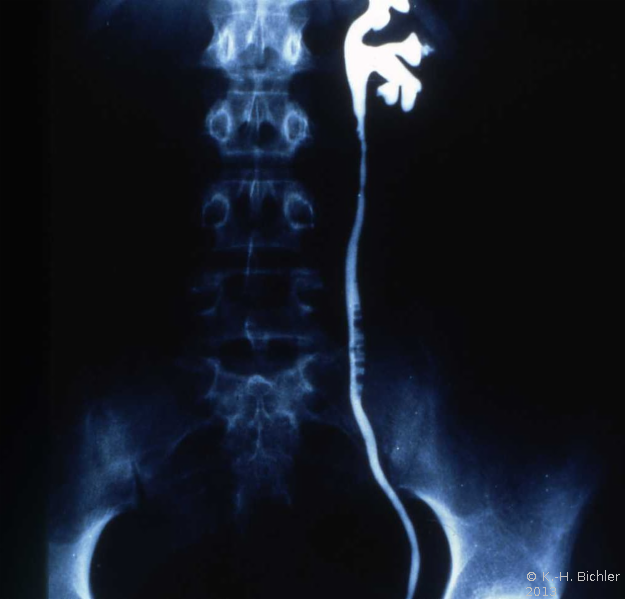

Das Ausscheidungsurogramm ergab eine stumme Niere links (Abbildung 18c). Die retrograde Sondierung zeigte eine deutlische Kompression des Harnleiters sowie eine verkleinerte Niere links mit destruierten Kelchen (Verplumpung) (Abbildung 18d).

Die Röntgenübersicht der Niere und ableitenden Harnwege zeigten keinen Anhalt für Konkrement. Im Ausscheidungsurogramm eine "stumme Niere" links (Abbildung 19a). Bei der retrograden Sondierung links fand sich keine Abflussbehinderung (Stein oder Stenose) (Abbildung 19c). Im MCU kein Anhalt für Reflux (Abbildung 19b). Im Nierenfunktionsszintigramm MAG3 wurde eine seitengetrennte Funktionsverteilung von rechts zu links wie 93% zu 7% festgestellt. Zur Abklärung eventueller Gefäßalterationen erfolgte eine Renovasographie mit dem Nachweis einer langstreckigen Stenose der linken Arteria renalis (Abbildung 19d). Wegen des Verdachtes auf eine generalisierte Arteriitis wurden Angiographien weiterer Gefäßgebiete durchgeführt: Dabei fanden sich eine geringgradige Einengung der infrarenalen Aorta und der linken Arteria subclavia.